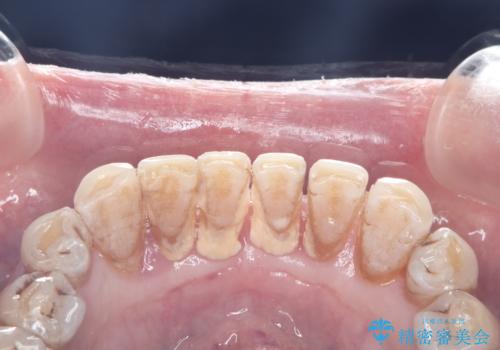

- 歯周病が進行されていているため歯肉が下がり歯根も露出してるためブラッシングが大変とのこと。

プラークや歯石が付着しやすい。

歯茎の中にもある歯石を何回かに分けて除去。

中程度から重度の歯周病で初期治療が終わりこれから定期的なメンテナンスをしていく予定です。